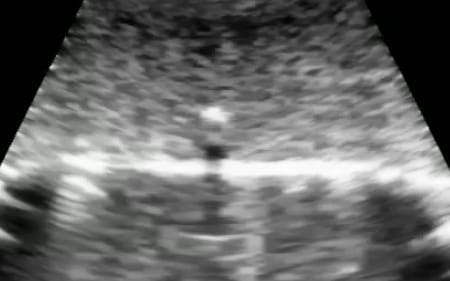

活用領域の拡大

エコーの使用が可能で目的に応じて濃淡の調節も可能。

ウレタンやシリコン製のモデルと組み合わせることで、幅広い領域での活用を実現。